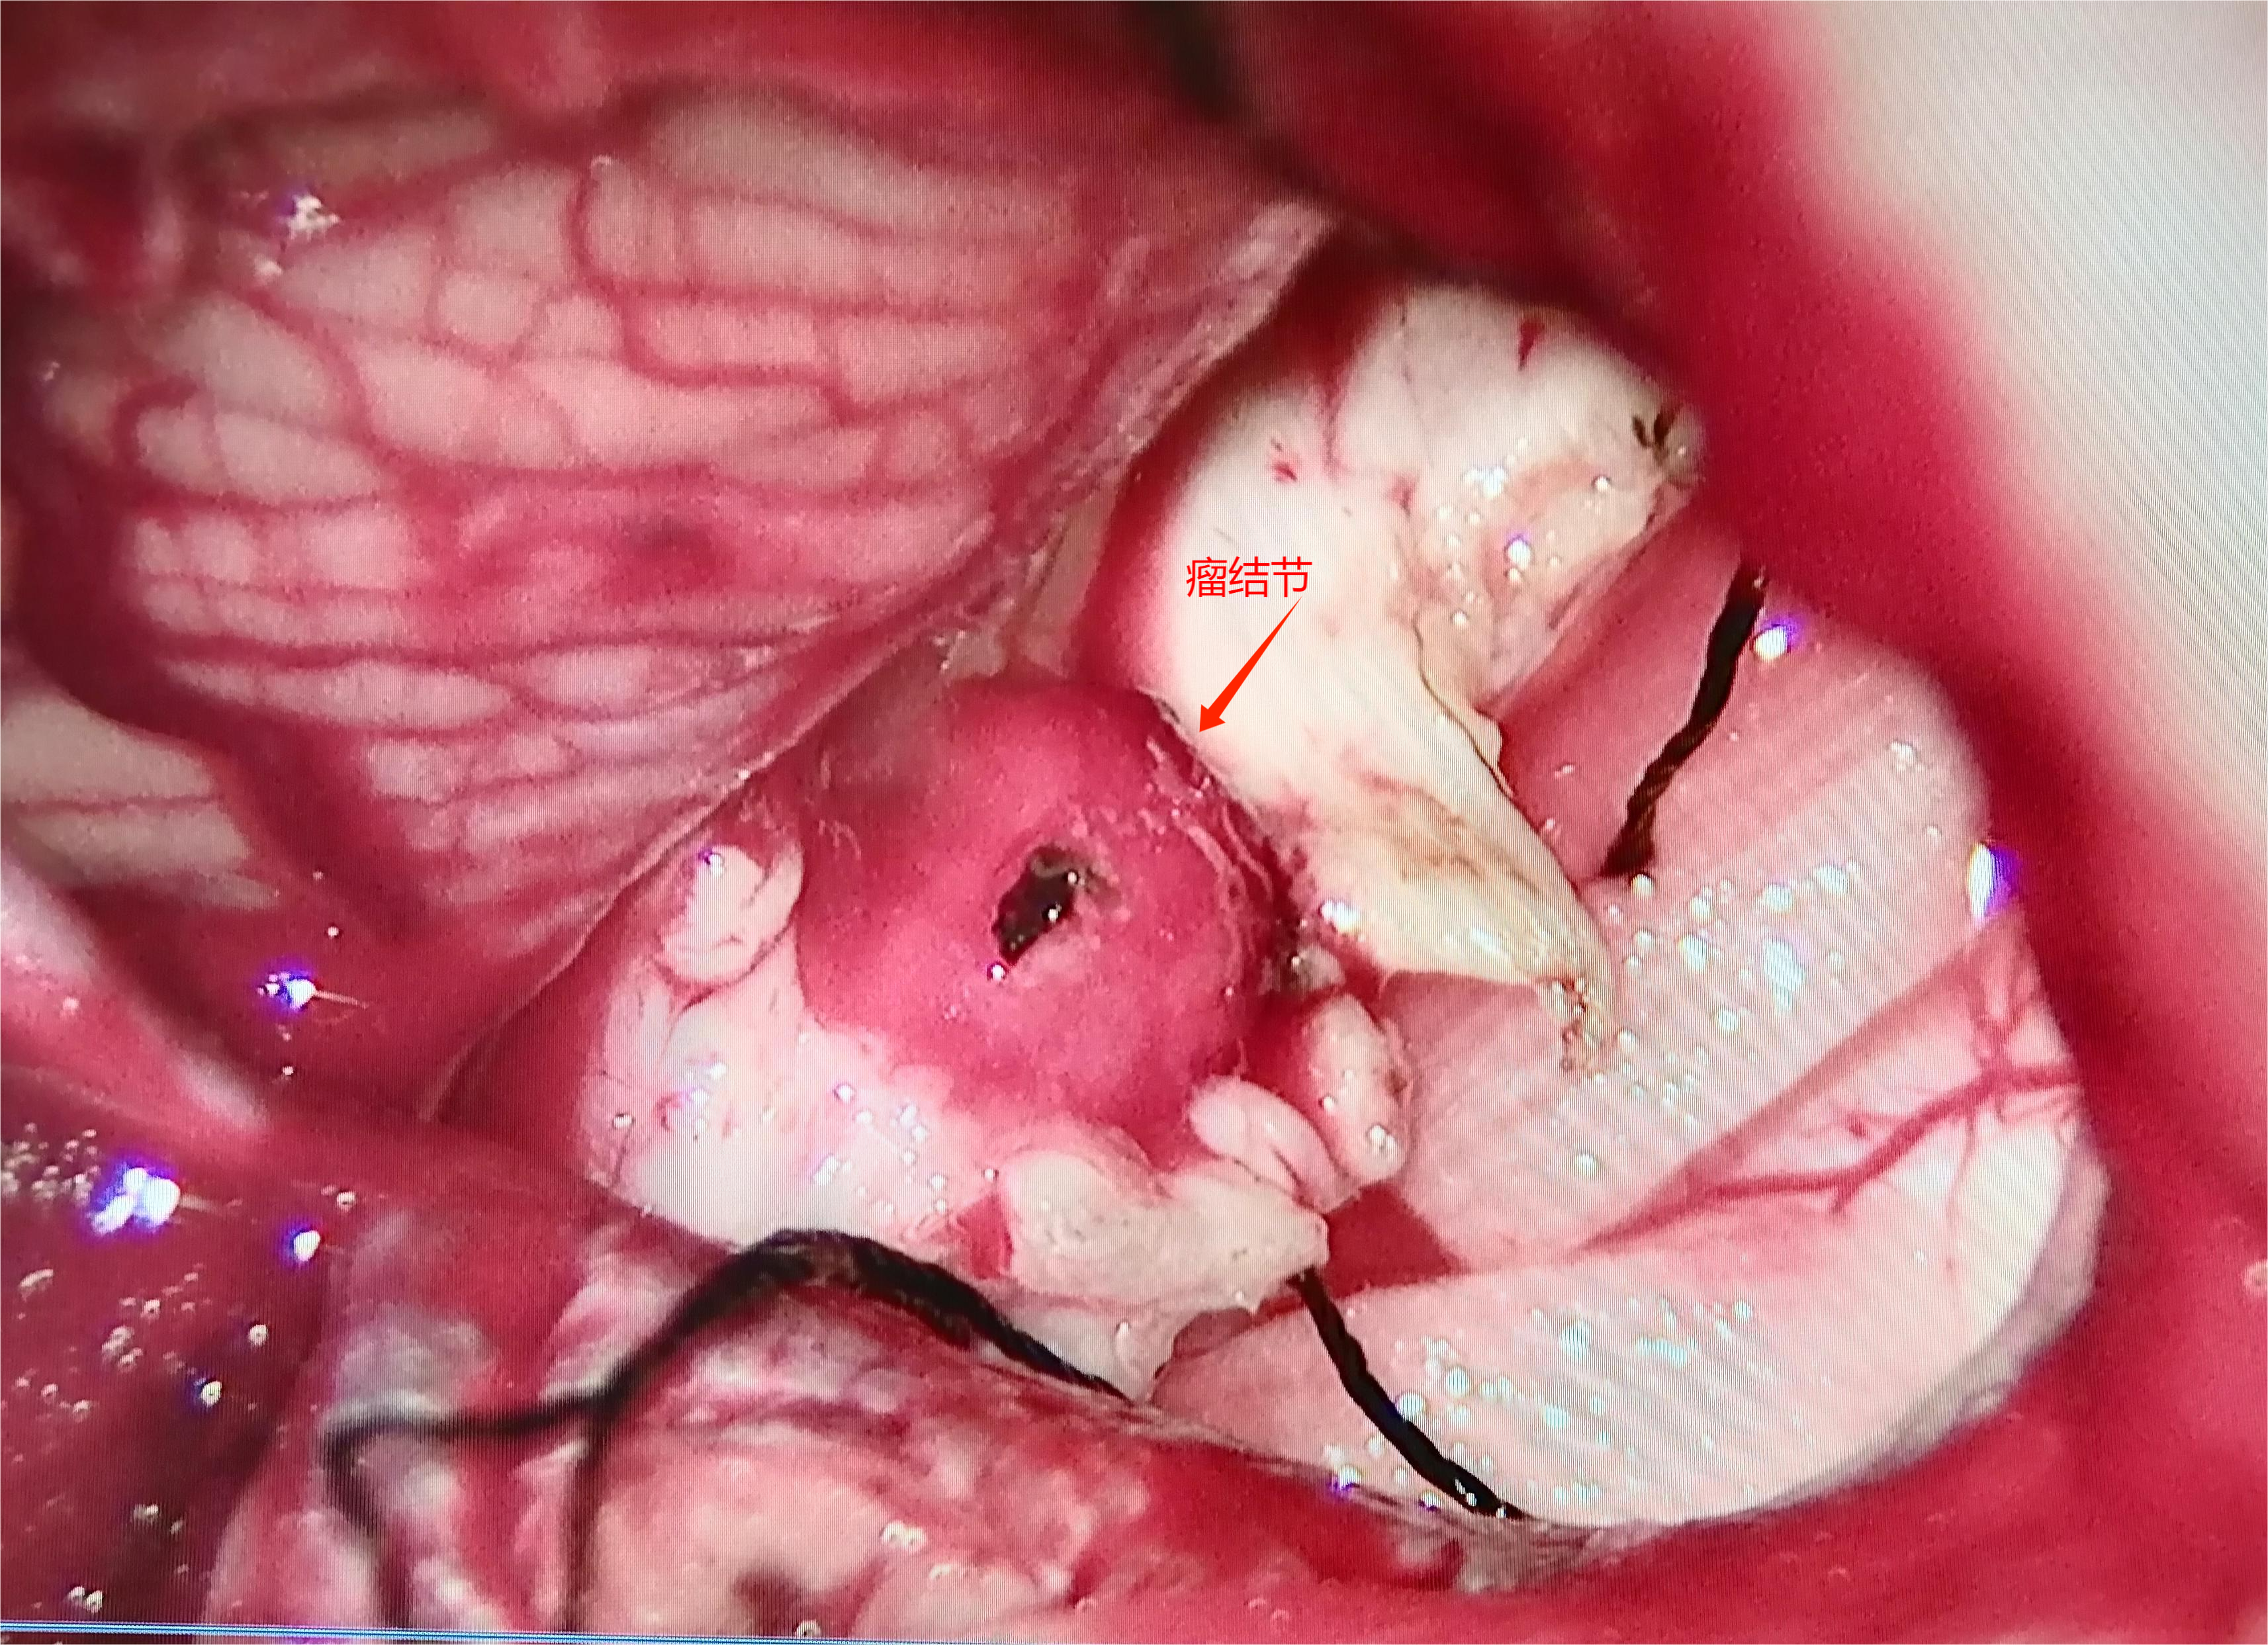

术中情况